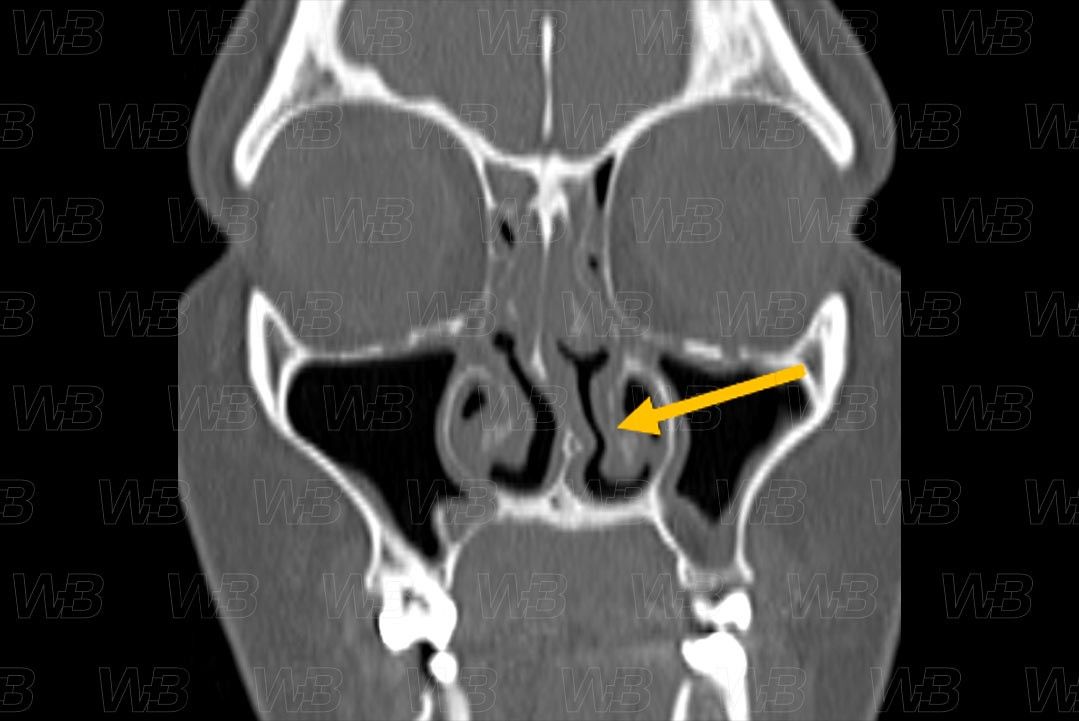

Texto alternativo para a imagem Figura 3. Créditos: Dra. Elazir Mota - Rio de Janeiro/RJ

Descrição da figura 3 e 4: Tomografia computadorizada dos seios paranasais evidenciando desvio da porção cartilaginosa do septo nasal para a esquerda (seta vermelha) e da sua porção óssea, visualizada nos cortes mais posteriores (seta amarela). Note ainda o preenchimento das células etmoidais e espessamento mucoso nos seios maxilares.